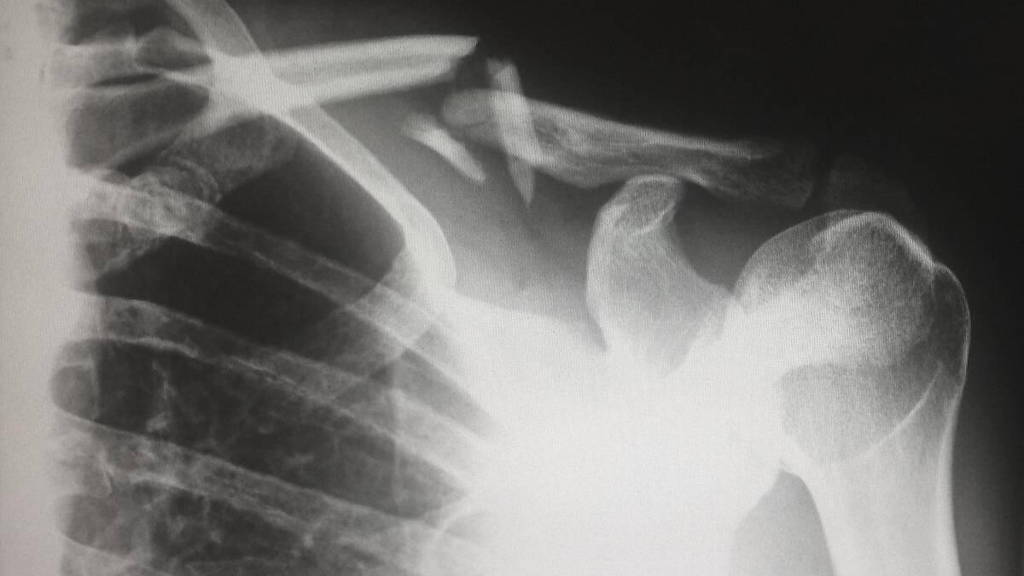

Sinds 15 maart hebben patiënten met een MijnOLVG-account toegang tot de beelden die horen bij een radiologieverslag. Daarmee is OLVG een van de eerste ziekenhuizen in Nederland die deze functie aanbiedt. Voorheen konden patiënten namelijk alleen het verslag van een radiologie-onderzoek bekijken in MijnOLVG. Wilden ze de beelden zien die tijdens het onderzoek werden gemaakt, dan moesten ze de radiologiebeelden opvragen via het Patiënten Servicepunt.

De radiologiebeelden die de patiënt nu kan bekijken in MijnOLVG staan niet op zichzelf. Deze horen bij een verslag en een conclusie van de radioloog. Zodra het verslag via MijnOLVG is vrijgegeven door de zorgverlener, kunnen de beelden bekeken worden.